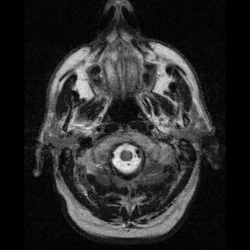

Neuroferritinopathy is most commonly diagnosed using MRI and other neuroimaging techniques.[1] MRIs help identify the iron deposits in the cerebellum, basal ganglia, and motor cortex common to neuroferritinopathy.[8] MRIs of affected individuals also show mild cerebellar and cerebral atrophy, or tissue breakdown, and gas cavity formation in the putamen.[8] Most importantly, the MRIs show misfolded ferritin proteins and iron deposits in the glial cells of the caudate, putamen, globus pallidus, cerebral cortex, thalamus, and purkinje cells, causing neuronal death in these areas.[8]